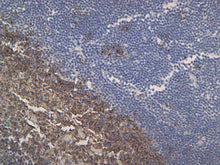

Description: This monoclonal antibody targets the C-terminal (intracytoplasmic) epitope of CD20, which is a 33 kDa leukocyte surface antigen that plays a role in the development and differentiation of B-cells into plasma cells. Although CD20 has been shown to be expressed from pre-B-cells and persisting through B-cell maturation until differentiation into plasma cells it has also been reported in low levels on normal and neoplastic T-cells.

Studies have shown that CD20 is a reliable pan B-cell marker and in conjunction with a T-cell marker (CD3) for immunophenotyping B-cell lymphomas from T- and null-cell lymphomas.

Positive Control: Lymph node, tonsil, or B-cell lymphoma